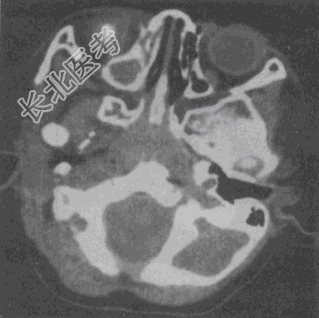

- 单项选择题女性,14个月。发现视力低下CT如图所示, 最可能的诊断是

A、脉络膜黑色素瘤

B、视神经胶质瘤

C、海绵状血管瘤

D、视网膜母细胞瘤

E、眼底出血